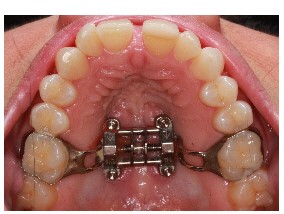

We recognize many adults need expansion treatment but that becomes more difficult as we age. Adults with sleep disordered breathing present with many symptoms that can include, snoring, open mouth breathing, sleep apnea, upper respiratory resistance syndrome, and trouble falling or staying asleep. The goal is to determine why these symptoms are present and what can be done to improve the patient’s quality of life with appliances or surgical recommendations. Dr. Kuhta uses specialized bone supported expanders to change the shape of the jaw and not just mask the problem. Every treatment plan is specialized to your needs and aims to alter the way in which you breathe. Dr. Kuhta offer’s non-surgical and minimally invasive surgical options to expand or widen the upper jaw. Using bone-based expanders the goal is to widen the jaw and not just tip the teeth. By expanding the jaw with TAD-based (or mini implant) expanders, you can improve airway, increase room for the tongue, open the nasal cavity and correct crossbites. Skeletal expansion on adults can be life changing! If you are interested in the maxillary skeletal expander (MSE) your next step is scheduling an airway consultation. From there we determine if you are a possible candidate and progress to 3-D imaging to evaluate the probable success of expansion. Before your appointment if you would like to research MSE appliances, Dr. Kuhta would be happy to answer any specific questions.